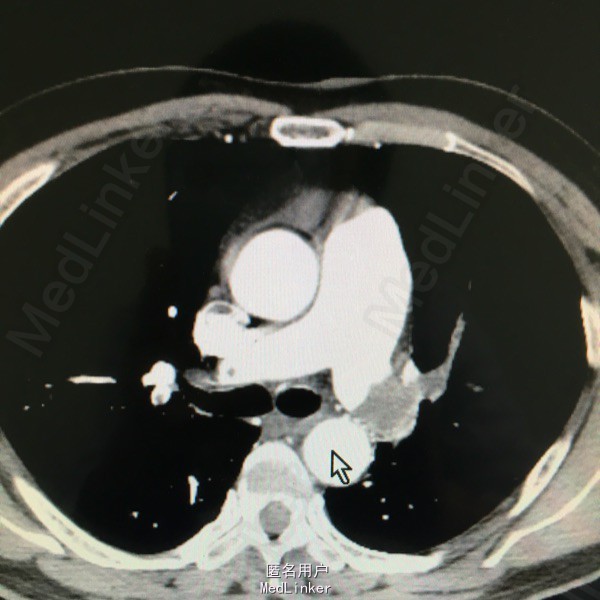

男性,61岁,因气紧3天入院。平时剧烈活动或活动量加大后感气紧。8年前有下肢深静脉血栓,后一直口服阿司匹林。

入院查体见呼吸较平稳,氧饱和度95%左右,嘴唇发紫;CT提示双肺大面积动脉栓塞,心脏彩超提示肺动脉高压,双下肢彩超未见静脉血栓。

慢性肺动脉栓塞,正规抗凝溶栓治疗

对于肺动脉栓塞来讲多数是由于下肢静脉血栓脱落所致,可予以置入腔静脉滤器同时介入下捣栓溶栓。但该患者下肢已无血栓,而且通过症状来看考虑慢性肺动脉栓塞,予以长期正规抗凝治疗十分重要。